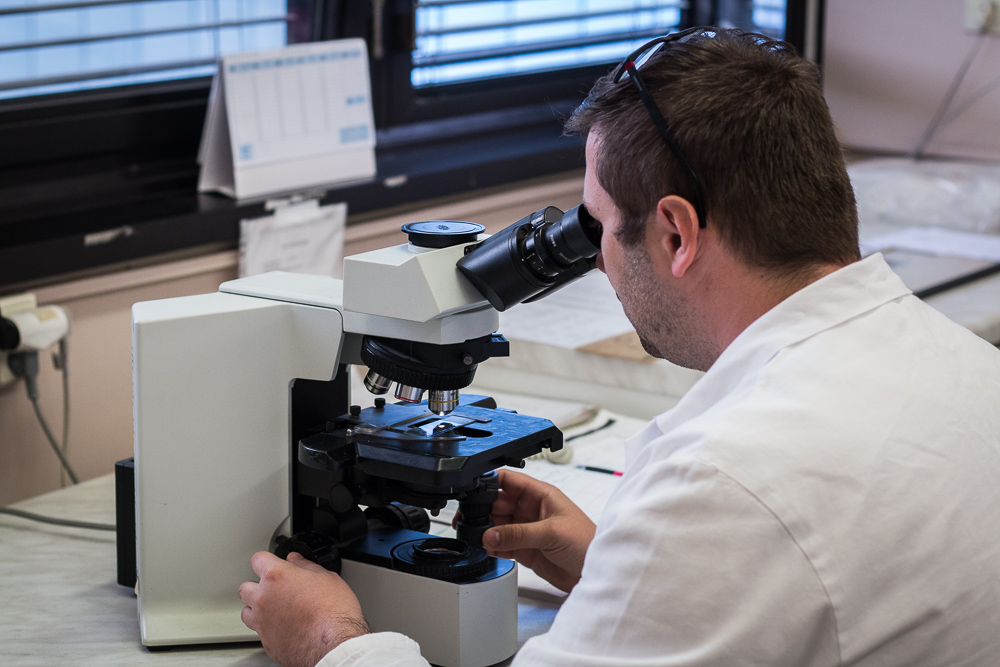

Nosným úkolem ve zdravotnictví je zabezpečení diagnostiky a typizace chorob nemocných operovaných nebo nemocných, u kterých byly odebrány vzorky buněk nebo tkání jiným než chirurgickým operativním přístupem (endoskopické odběry, jehlové punkce, stěry buněk) ve Fakultní nemocnici Motol a Homolka. Část vyšetření probíhá v rámci takzvaných peroperačních biopsií prováděných v průběhu operace a jejichž výsledek ovlivňuje rozhodování operatéra o dalším průběhu operace. Část vyšetření prováděných na pracovišti slouží ke stanovení prognózy některých onemocnění, kontrole odpovědi onemocnění na léčbu, nebo k indikaci pro cílenou specifickou terapii pacientů. Pitevním provozem pracoviště plní edukační a kontrolní funkci v rámci Fakultní nemocnice Motol a Homolka a 2. lékařské fakulty Univerzity Karlovy v Praze.

Diagnostikou onemocnění různých systémů se zabývají týmy školených pracovníků – lékařů a biologů s pomocí laborantek ve specializovaných laboratořích.

Zdravotní laborant pro histologii – praktická část

Zdravotní laborant pro histologii – praktická část